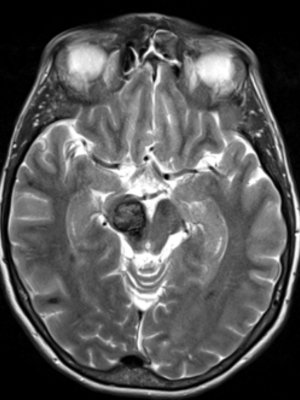

Cavernous Malformations

Our research focus in cavernous malformation has aimed at identifying imaging characteristics, follow-up strategies, and decision analysis for surgical candidates based on the location of the lesion and history of bleeding. Additionally, our team has collaborated in the development of multiple national and international clinical guidelines.